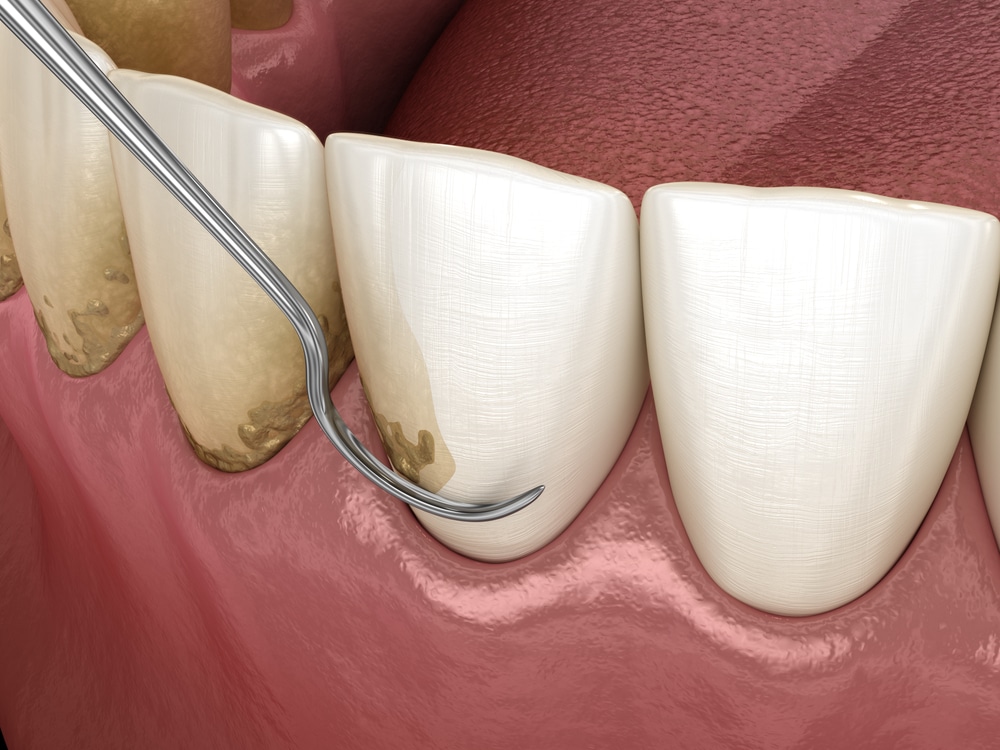

Küretaj, diş eti hastalıklarının tedavisinde uygulanan, derinlemesine temizlik sağlayan özel bir diş tedavi yöntemidir. Normal diş taş temizliği yalnızca dişlerin görünen yüzeyindeki tartarları ve plakları ortadan kaldırırken; küretaj, diş etlerinin altına inerek diş eti ceplerinde biriken bakteri, iltihap ve sertleşmiş tartarları temizler.

- Küretaj işlemi sırasında, diş eti cebine girilerek plak ve tartarlar özel küret adı verilen aletlerle uzaklaştırılır.

- Bu sayede diş eti dokusunun tekrar sağlıklı bir şekilde dişe tutunması sağlanır.

- Derin temizlik: Küret adı verilen özel aletlerle diş eti ceplerinde biriken plak, tartar ve bakteriler özenle temizlenir.

- Kök yüzeyi düzleştirme (root planing): Diş köklerindeki pürüzlü yüzeyler temizlenir ve düzeltilir. Böylece bakterilerin yeniden tutunması zorlaşır.